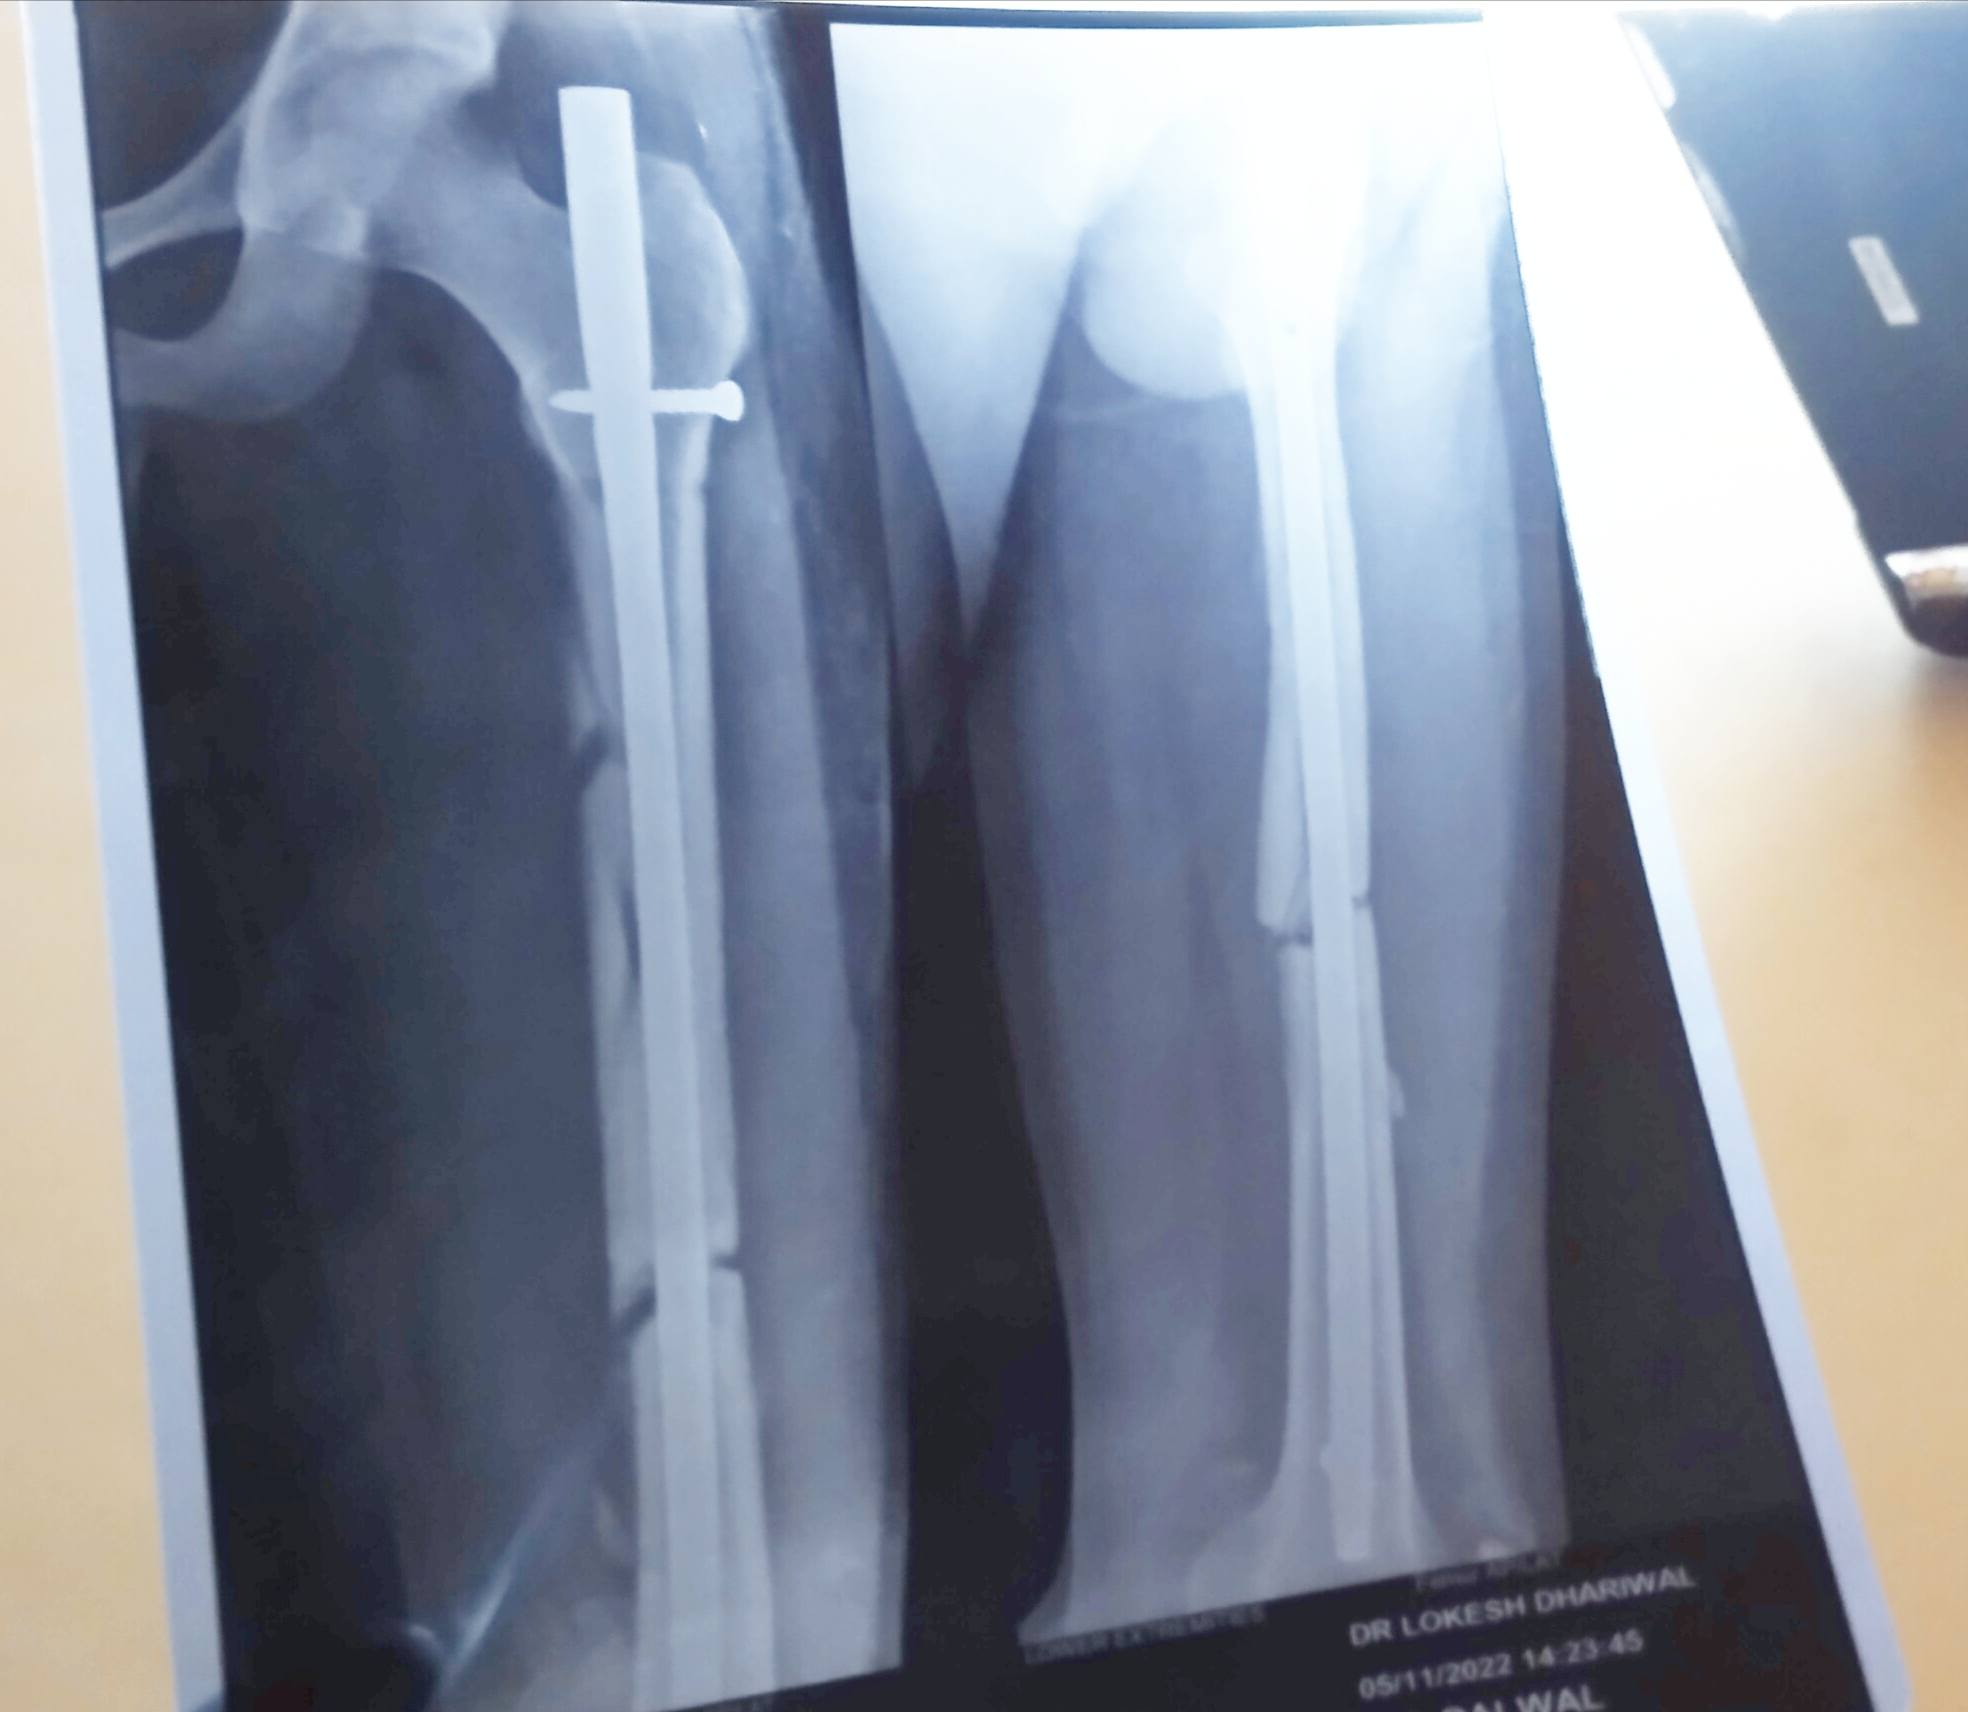

sir i wanna know that i haveno bone transformation in my x ray.Because when i done my first x ray after 1month of surgry but in second x ray which is done on 2month 25 day after surgery it hs not result.what should i hve to do mujhe abhi 3 mhinne hue hn femoral shaft displaced fracture tha

ye mere 2month 25 day bad ka h x ray

aur phle mne apko 1 month post surgery k bhja tha